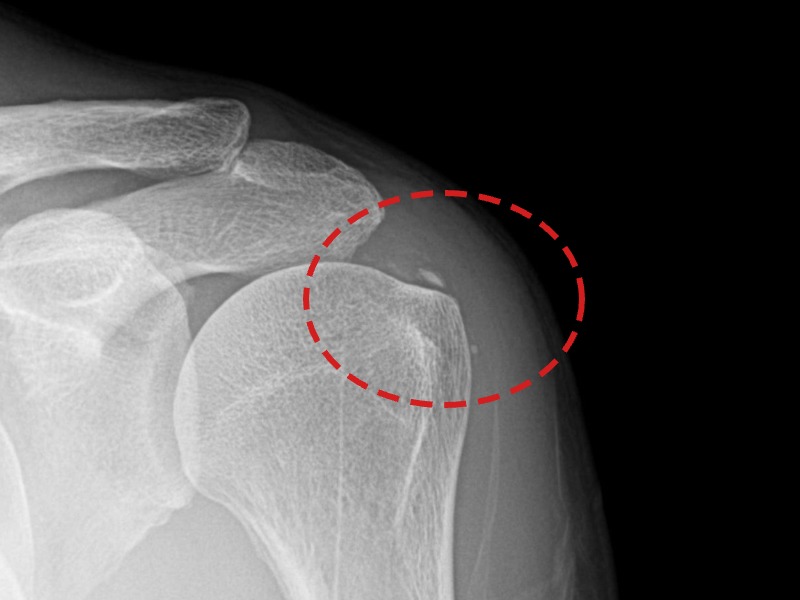

[촬영시기:21.10.21~21.10.30]

[석회분쇄흡입술] 우측 어깨 통증과 운동 제한으로 일상생활이 불편해진 30대 여성 환자로, X-ray에서 우측 극상근건 내 석회 침착이 확인되어 석회분쇄흡입술을 시행하였습니다.